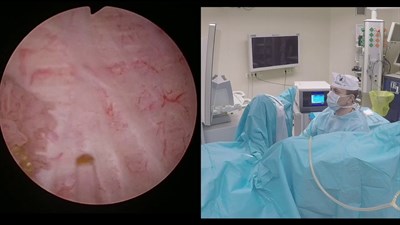

- Полный спектр оперативных вмешательств при урологических и онкоурологичсеких заболеваниях. Является одним из основоположников в России лазерной энуклеации гиперплазии простаты и лазерной эн-блок резекции стенки мочевого пузыря с опухолью. В приоритете малоинвазивные и органосохраняющие вмешательства.

- Лазерная (тулиевая ThuLEP и гольмиевая HoLEP) энуклеация аденомы простаты.

- Электрохирургическая (TUEB) энуклеация аденомы простаты.

- Лазерная эн-блок резекция стенки мочевого пузыря с опухолью.

- Ретроградная интраренальная хирургия (RIRS) при камнях почек.

- Является одним из пионеров внедрения в Российской Федерации методик энуклеации аденомы простаты и эн-блок резекции стенки мочевого пузыря с опухолью при помощи гольмиевого и тулиевого волоконного лазеров и остается ведущим специалистом в данной области.